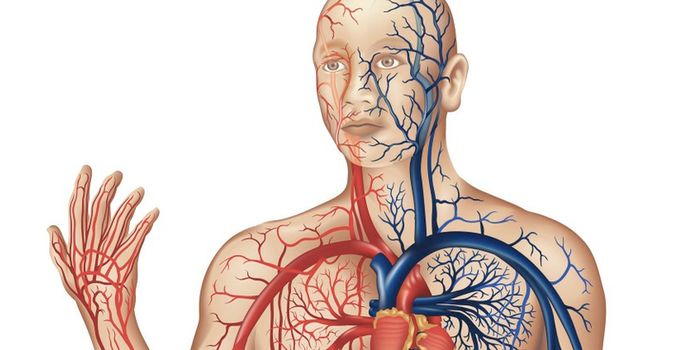

OCT 04, 2018CardiologyThe video above is a student's perfect companion to any intro to an anatomy course. As for those studying the anatomy of ...